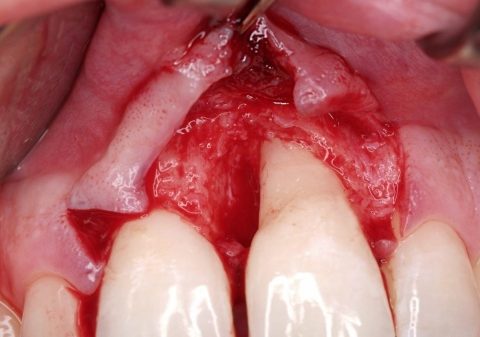

Bei der Freilegung zeigte sich eine vollständige Obliteration des vestibulären Raums mit fehlender befestigter Schleimhaut – sowohl im anterioren als auch im posterioren Bereich. In der Abteilung XXIII des Bundeswehrkrankenhauses Berlin erfolgte daraufhin die vestibuloplastische Rekonstruktion nach modifizierter Edlan-Mejchar-Technik. Es wurden sechs zugeschnittene Mucograft®-Membranen auf die periostale Fläche aufgebracht und mit Einzelknopfnähten fixiert. Zur Abdeckung diente ein intraoperativ verlängerter Interimsersatz, der postoperativ als Verbandplatte fungierte.